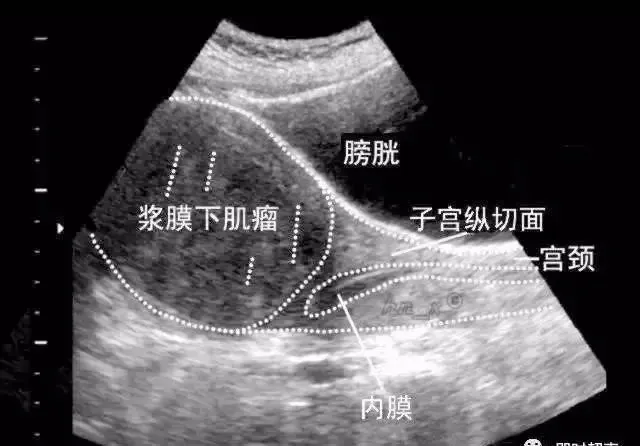

浆膜下肌瘤

子宫肌层内异常回声结节向浆膜下突出,使子宫变形;或完全突出宫体的浆膜下肌瘤,仅与宫体以一蒂相连;或向两侧突出则形成阔韧带肌瘤。